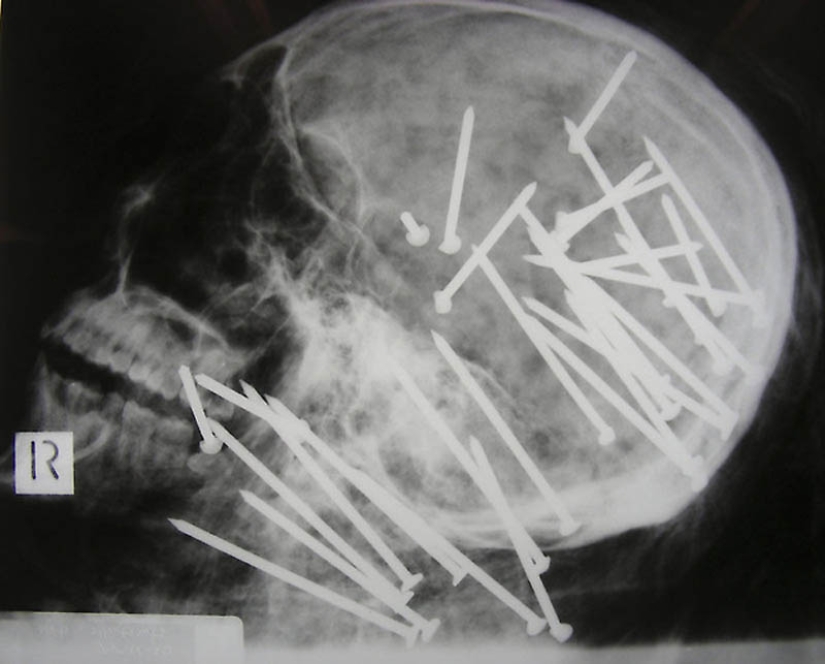

1. El cráneo de un hombre chino que recibió un disparo en la cabeza con un martillo neumático